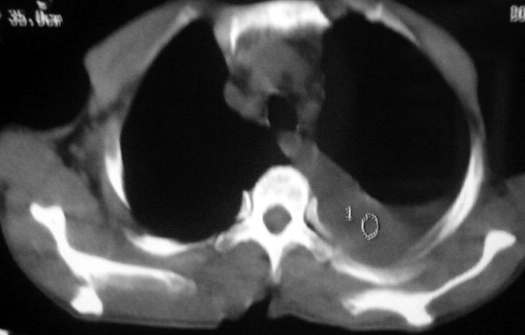

男,54岁,咳嗽,气喘半年,胸痛一月.

血性胸水

左侧胸腔积液 斜裂积液 心包积液 左肺不张 考虑左肺ca并胸膜心包转移。

支持左肺下叶中心型肺癌(累及舌叶)伴阻塞性肺炎、膨胀不全、胸腔积液、心包少量积液。

考虑左肺下叶中央型肺癌伴阻塞性肺炎及肺不张,纵隔受累可能,胸膜转移。

1.左肺下叶中心性肺癌伴阻塞性肺炎,肺不张.

2.左侧胸腔积液,心包积液